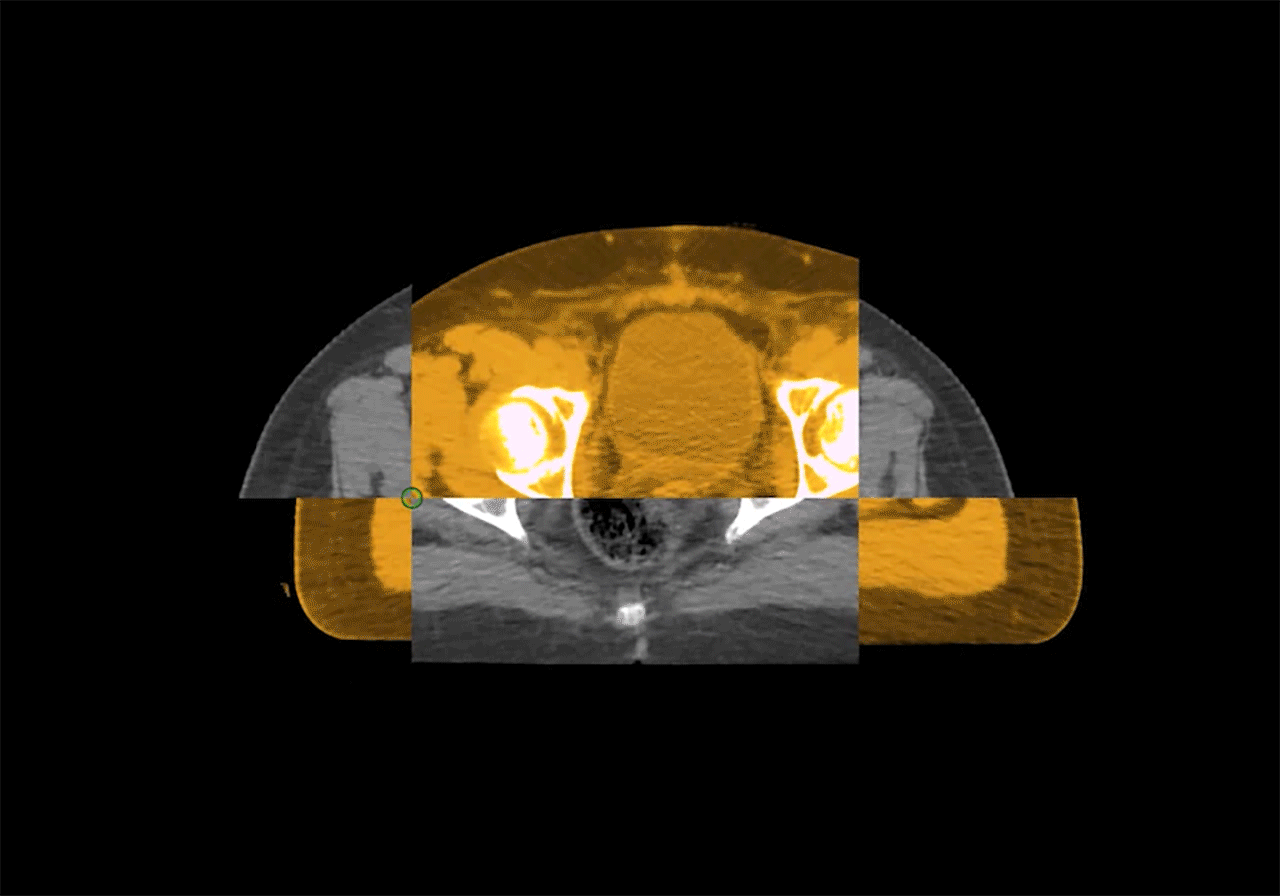

Înregistrare deformabilă automatizată

Funcția de înregistrare deformabilă automatizată, bazată pe imagini CT de calitate diagnostică, permite corelarea precisă a structurilor anatomice în diferite etape ale tratamentului. Această tehnologie asigură protecția optimă a organelor la risc (OAR) și menține acuratețea maximă în livrarea dozei de radiație, contribuind la eficiența și siguranța radioterapiei.

Aplicarea radioterapiei adaptive online (ART) în cancerul orofaringian

Pe parcursul tratamentului radioterapic, se observă o reducere semnificativă a dimensiunii tumorii la pacienții cu cancer orofaringian. Folosirea planului inițial de tratament, fără adaptare, ar fi dus la iradierea inutilă a măduvei spinării și a glandelor parotide. Prin utilizarea tehnologiei Online ART, planul terapeutic este ajustat automat pentru a reflecta modificările volumului țintă, reducând astfel doza de radiație administrată structurilor sensibile și crescând siguranța tratamentului.

Aplicarea radioterapiei adaptive online (ART) în cancerul de col uterin

Comparativ cu utilizarea planului original bazat pe IGRT, planul adaptiv online (Online ART) permite reducerea iradierii inutile a vezicii urinare și îmbunătățește conformitatea dozei administrate zonei țintă. În plus, acest tip de planificare reduce doza de radiație asupra măduvei spinării până la 35 Gy, asigurând un echilibru optim între eficiența terapeutică și protecția țesuturilor sănătoase.